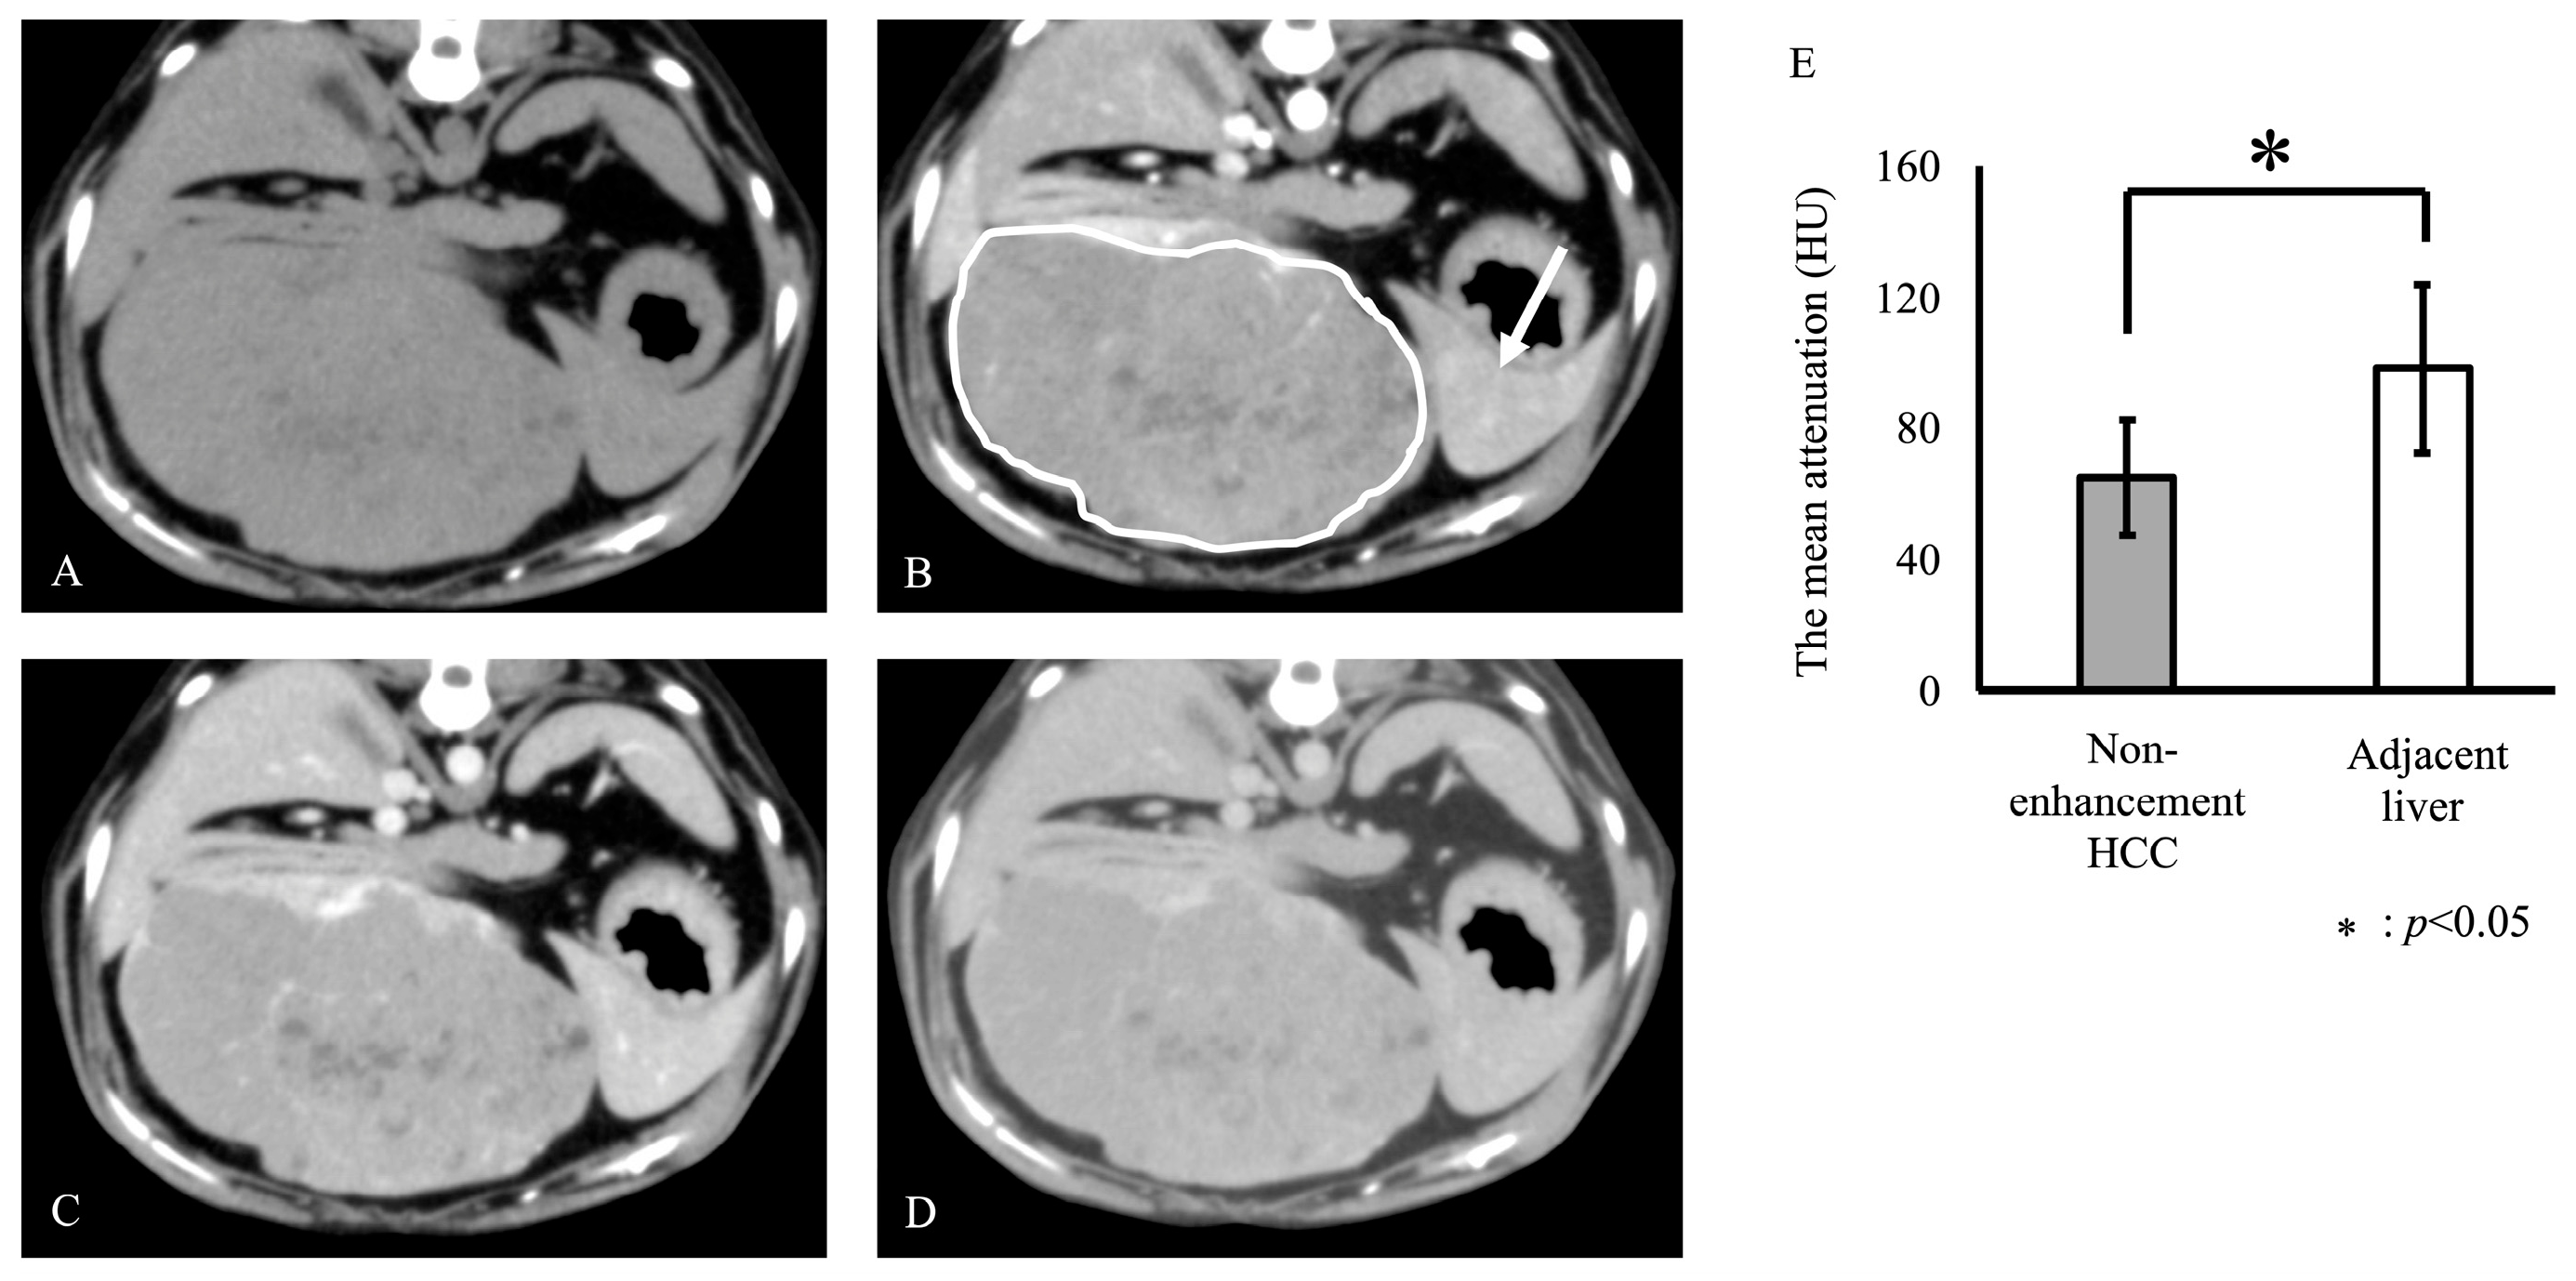

3. Results